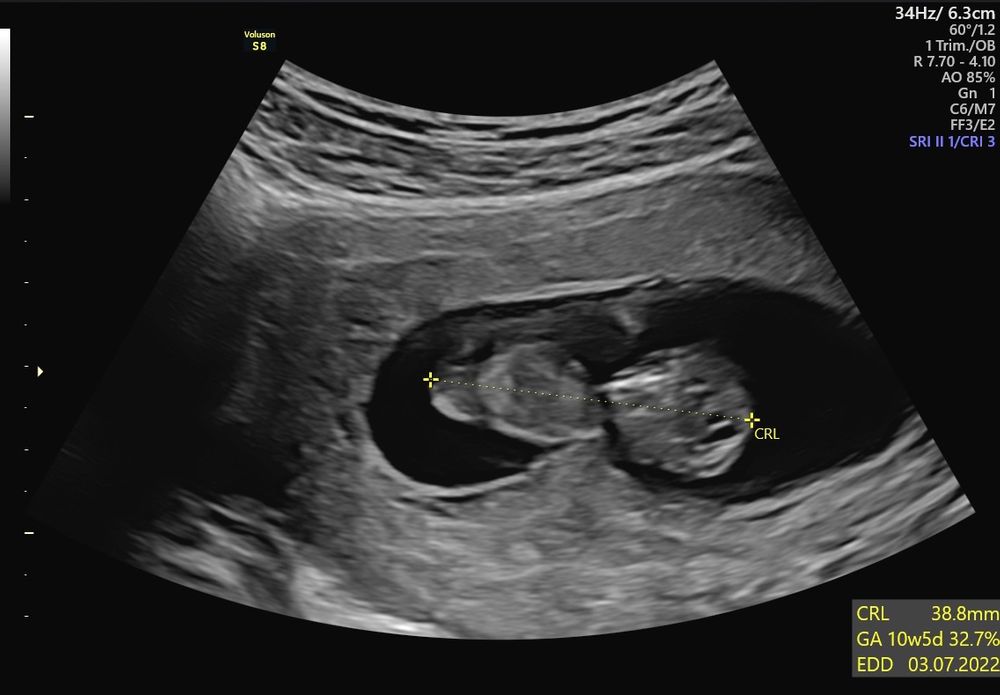

Сегодня сходила к врачу на узи молочных желёз. Так как есть мастопатия . Фиброаденомы и кисты. Все норм. И заодно посмотрела человека. Почти 4 см. Шевелился во время узи. Показали ножки.